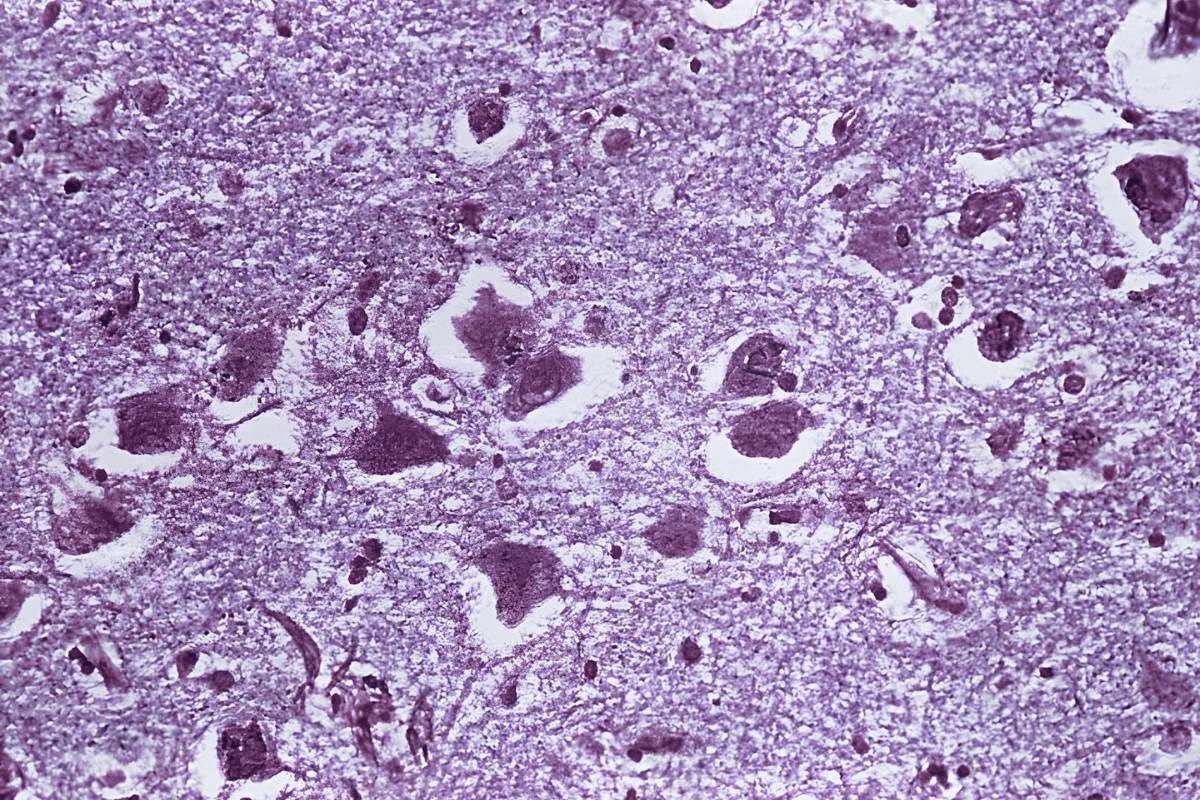

Neurological Conditions Associated with Involuntary Mouth Movements

Lip smacking and other abnormal mouth movements are common in the elderly. These movements can affect their quality of life and health. They are a concern for both patients and their caregivers.

Parkinson’s Disease and Parkinsonian Symptoms

Parkinson’s disease is a disorder that causes tremors, stiffness, and movement problems. Involuntary mouth movements, like lip smacking, can happen in Parkinson’s patients. This is more common in those taking long-term dopaminergic medications.

Parkinsonian symptoms, caused by some medications, can also lead to abnormal mouth movements. These symptoms can look like Parkinson’s disease. They include rigidity, slow movements, and tremors.